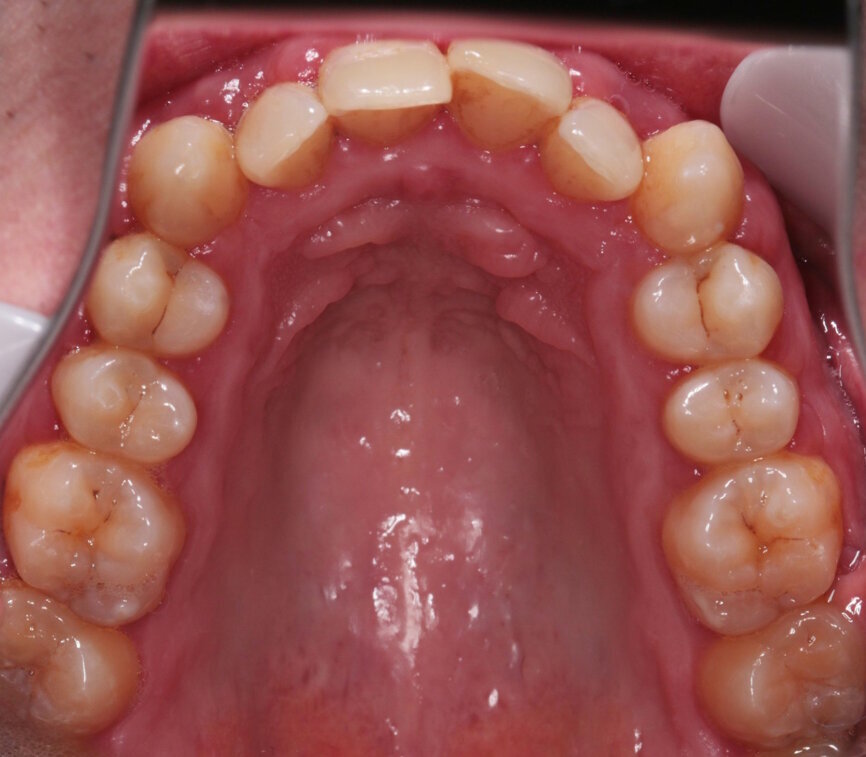

Fig. 6: Pre-treatment lower occlusal view

I explained that the maxillary teeth could and should be aligned, as this would likely result in easier cleaning of the teeth, plus it would improve the appearance. The patient and I agreed that the mandibular teeth could remain untouched, as this would keep the cost down, but mainly because they did not bother him. The priority was to stabilise his periodontal condition. A basic periodontal examination Code 3 and heavy bleeding were recorded in each sextant. At that visit, I performed a gross scaling using the ultrasonic scaler and used a model to demonstrate both the use of flossettes and an oscillating toothbrush.

A 32-year-old male patient presented to our practice after he saw that we provide GDP orthodontics on our website. He came from an NHS practice and it was agreed that he would remain with that practice for his routine care. He was fit and well, took no medication, had no allergies and was a non-smoker. However, he was struggling with his oral hygiene and did not like the appearance of his maxillary teeth, specifically the colour and the alignment. He was not keen on the idea of fixed orthodontic appliances, but had heard about clear aligners.